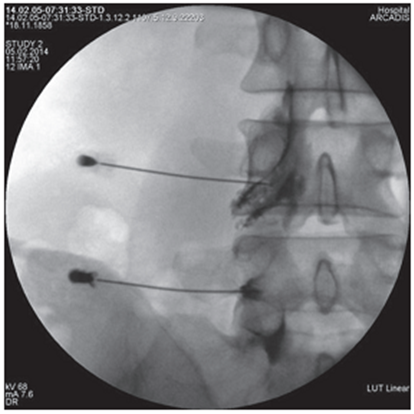

Figure 5. Intraoperative X-ray of the lumbar spine in frontal projection. Puncture of the first sacral foramen and spread of contrast along the root S 1 |